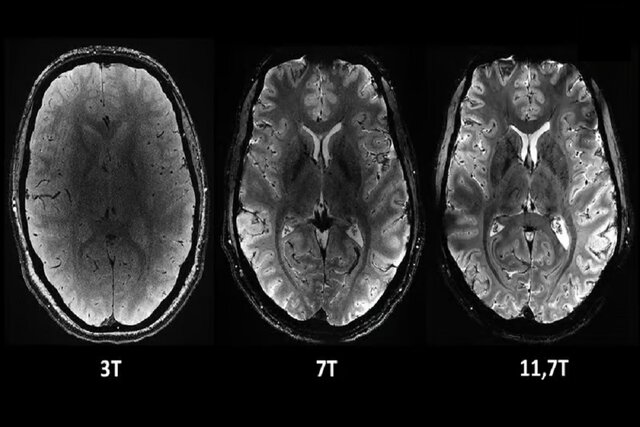

دستگاه امآرآی «Iseult» که توسط کمیسیون انرژیهای جایگزین و انرژی

اتمی فرانسه(CEA) توسعه یافته است، دارای قدرت میدان مغناطیسی ۱۱.۷ تسلا(T)

است. در مقایسه باید گفت که قدرت میدان مغناطیسی دستگاههای امآرآی

معمولی که امروزه در بیمارستانها به طور گسترده مورد استفاده قرار

میگیرند، معمولا ۱.۵ یا حداکثر سه تسلا هستند.

به نقل از نیواطلس، مزیت اصلی این قدرت اضافی این است که میتوان

تصاویری با وضوح بسیار بالاتر و بسیار سریعتر از مغز گرفت. تنها در عرض

چهار دقیقه، این دستگاه میتواند تصاویری تا ۰.۲ میلیمتر دقت از بافت مغز

را به صورت افقی ثبت کند. این حجم معادل چند هزار نورون در یک لحظه است.